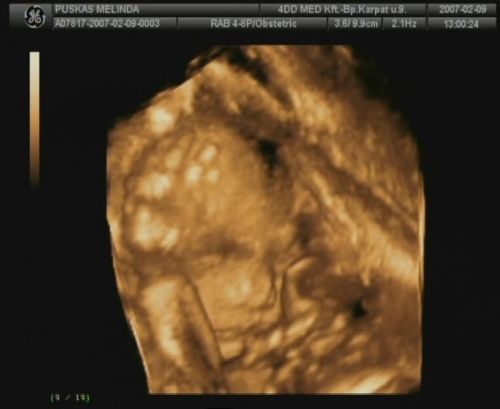

Sziasztok, megjöttem a 4D-ről. Sajnos most nincs időm a dvd-ről kimentegetni a képeket, de a telcsivel azt a hármat lefotoztam, amit kaptunk, remélem, hogy kivehető lesz azért számotokra a lényeg!

A szülésem dátuma is 2007.05.25.-re módosult, illetve a tickeremet is átjavítottam esszerint! :)